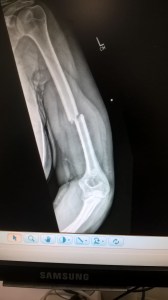

In the event it all happened quickly just after 1 am. I was wheeled to x-ray by the gentlest porter in the world, screeched in pain at the hands of the x ray woman, then wheeled back. The doctor came in soon afterwards and the image was flashed up on screen. A nice, clean, but total fracture of my humerus, mid-shaft and displaced – which explained why the side of my arm was bulging like Popeye’s.

The nurse, Dan, squeezed a dose of Oramorph into my mouth before telling me the bad news. He was going to fit me with a collar and cuff sling and it was probably going to hurt. No casts are applied for upper limb fractures, above the elbow or above the knee. My fracture was unlikely to need pinning – although the doctor promised to call in the morning after review with colleagues. The ‘conservative’ approach is preferred for bone setting wherever possible, rather than surgery. This meant I would most likely be left with my arm in a simple collar and cuff strap to allow the bones to align naturally, and sent home with an array of painkillers.